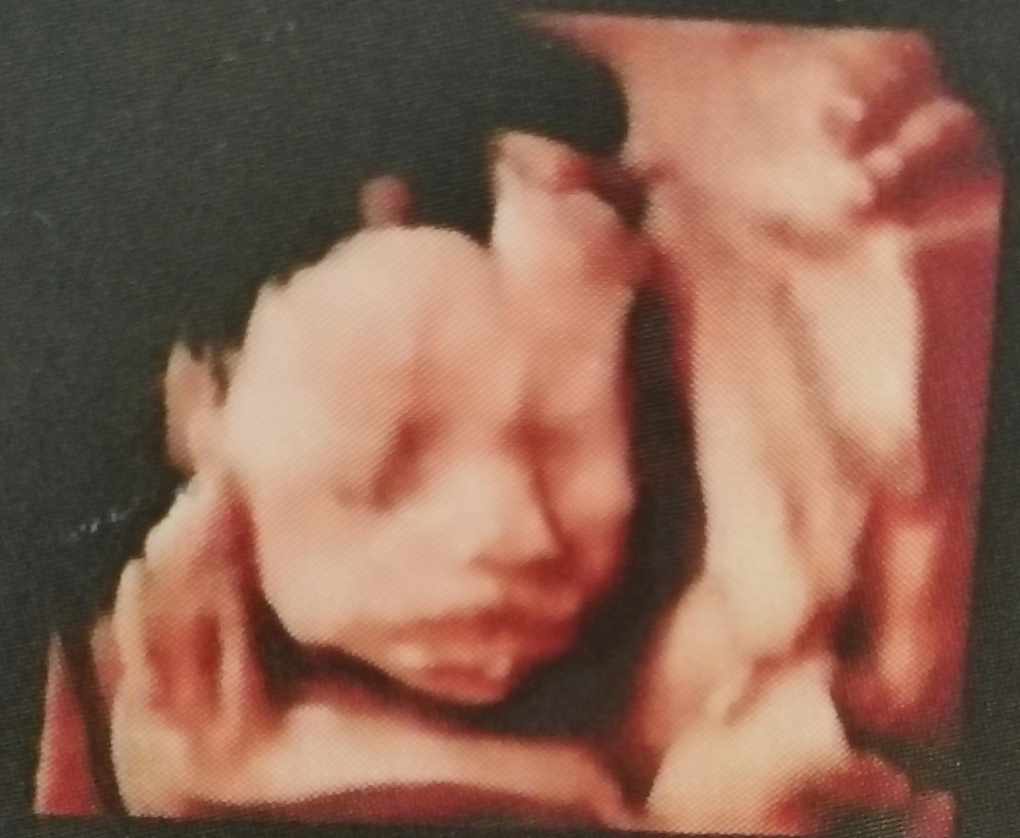

今天看见小宝贝的脸啦,开心~